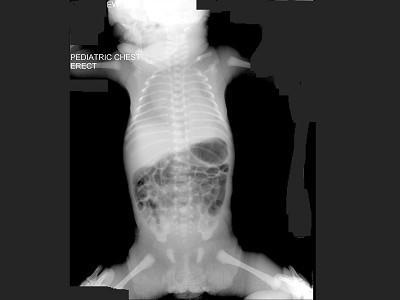

问题 早产儿,男,生后4小时,生后出现呼吸困难,如图,最可能的诊断为?(?)

选项 A.新生儿肺炎 B.新生儿湿肺 C.新生儿肺出血 D.新生儿特发性呼吸窘迫综合症 E.胎粪吸入综合征

答案 D